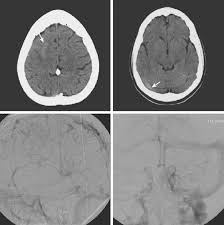

Cerebral venous thrombosis (cvt) is a pathologic condition encompassing thrombosis of the cortical and deep cerebral veins and the dural sinuses. Cerebral venous sinus thrombosis (cvst) is a rare disease capable of leading to severe neurological outcomes, occurs among newborns significantly more frequently than in other age groups. Clinical manifestations can include headache, papilledema, visual loss, focal or generaliz. Recommendations on the evaluation and management of cerebral venous thrombosis during pregnancy and in the pediatric population are provided. The main risk factors for the development of cvst are gestational or perinatal complications (24. Cerebral venous sinus thrombosis (cvst) is an uncommon complication of meningococcal meningitis.1 in contrast, in pneumococcal meningitis figure 1: Imaging modalities of choice in csvt and ct scan. What causes cerebral venous sinus thrombosis? Cerebral venous thrombosis (cvt) is an uncommon disorder in the general population. Cvst is an uncommon type of stroke. Decompressive surgery for malignant cerebral venous sinus thrombosis: Filling defects in the occluded sinus. Ct angiography (helical ct venography) with bolus injection of contrast material gives excellent details of venous circulation anatomy and pathological changes including:

Cerebral venous sinus thrombosis (cvst) is a clot in the venous drainage system of the brain and can present to ophthalmology. Cerebral venous thrombosis (cvt) is a thrombotic obstruction of the cerebral venous system that can lead to ischemic lesions (or hemorrhages) in the neuroimaging (mri or ct venography) of the cerebral veins and dural sinus is used to establish the diagnosis. Cvst is a rare form of stroke. Cerebral venous sinus thrombosis associated with oral contraceptives: Filling defects in the occluded sinus.

Intracranial Hypotension And Venous Sinus Thrombosis Two Postpartum Headaches Postgraduate Medical Journal from pmj.bmj.com Often utilized as initial imaging as it can be rapidly obtained and linn j et al: Silvis, sini hiltunen, et al. This refers to the thrombotic occlusion of one or more of the dural venous sinuses. Cerebral venous sinus density on noncontrast ct correlates with hematocrit. Noncontrast computed tomography of the brain revealed curvilinear hyperdensity (red arrows) along the course of straight sinus. For the cerebral venous sinus thrombosis study group. Thrombosis of cerebral veins and venous sinuses is a rare disease, which accounts for less than 1% of all cases of stroke. This condition may also be called cerebral sinovenous thrombosis.

Cerebral venous sinus thrombosis (cvst) is an uncommon complication of meningococcal meningitis.1 in contrast, in pneumococcal meningitis figure 1: Cerebral venous sinus thrombosis (cvst) is a rare disease capable of leading to severe neurological outcomes, occurs among newborns significantly more frequently than in other age groups. Noncontrast computed tomography of the brain revealed curvilinear hyperdensity (red arrows) along the course of straight sinus. Filling defects in the occluded sinus. Cerebral venous thrombosis (cvt) is an uncommon disorder in the general population.

Imaging Of Cerebral Venous Thrombosis Clinical Radiology from els-jbs-prod-cdn.jbs.elsevierhealth.com An unusual diagnosis and management of cerebral venous thrombosis: Cerebral venous sinus thrombosis as presenting feature of ulcerative colitis. Efns guideline on the treatment of cerebral venous and sinus thrombosis. Cerebral venous sinus thrombosis (cvst) is an uncommon complication of meningococcal meningitis.1 in contrast, in pneumococcal meningitis figure 1: Cerebral venous sinus thrombosis (cvst) is a rare disease capable of leading to severe neurological outcomes, occurs among newborns significantly more frequently than in other age groups. Residents and fellows contest rules | international ophthalmologists contest rules. Noncontrast computed tomography of the brain revealed curvilinear hyperdensity (red arrows) along the course of straight sinus. Thrombosis of cerebral veins and venous sinuses is a rare disease, which accounts for less than 1% of all cases of stroke.